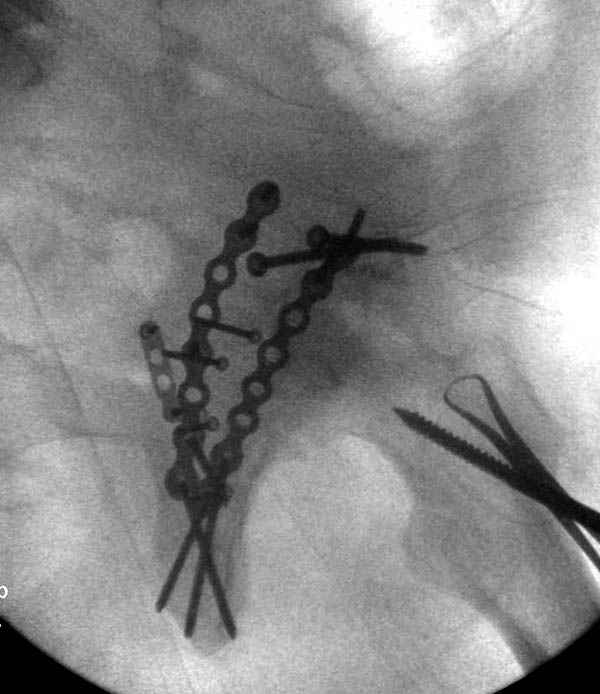

По снимку создается впечатление о высоком поперечном переломе, задней колонны, стенки; почему не пользовались *magic screw*?

Латеральное положение облегчает проведение тракции через вертел, за 5 мм стержень за вертел (грузом через тракционное приспособление), на обычном рентгенопрозрачном операционном столе, а для положения на животе, наверное, Judet Table более приемлем, потому что там имеется латеральное тракционное устроиство.

Там множество обычных 2.7 мм шурупов, потом идет фиксация основными пластинами.

Снимки здесь....